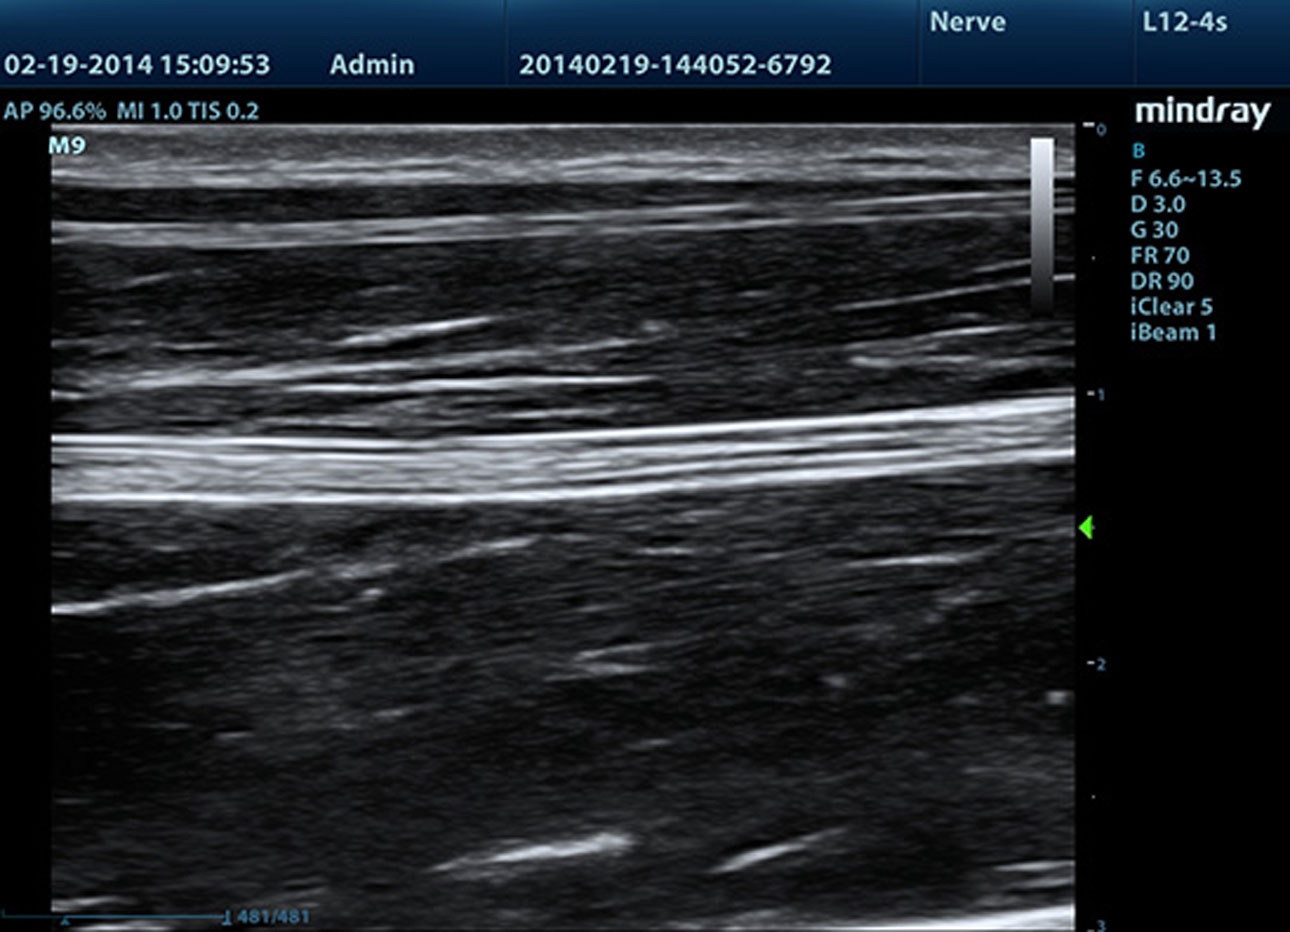

B-Steer/iNeedle?(Needle Enhancement Visualization)

Het instrument voor diepere biopsie: de scanline kan worden aangepast voor betere zichtbaarheid van de naald, zenuwen en kleinere vaten.